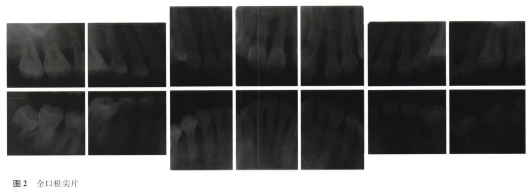

【体格检查】

口腔卫生状况差,大量软垢、牙石+++,全口牙龈色暗红、肿大,累及附着龈,牙龈质地松软,伴有龈裂,部分牙位的牙龈呈球状增生,盖过牙合面,触之易出血。

牙周探诊深度4~10mm,出血指数为4,可探及附着丧失,未及牙松动。13和23前突,腭盖高拱,语音不够清晰,上前牙散在间隙。